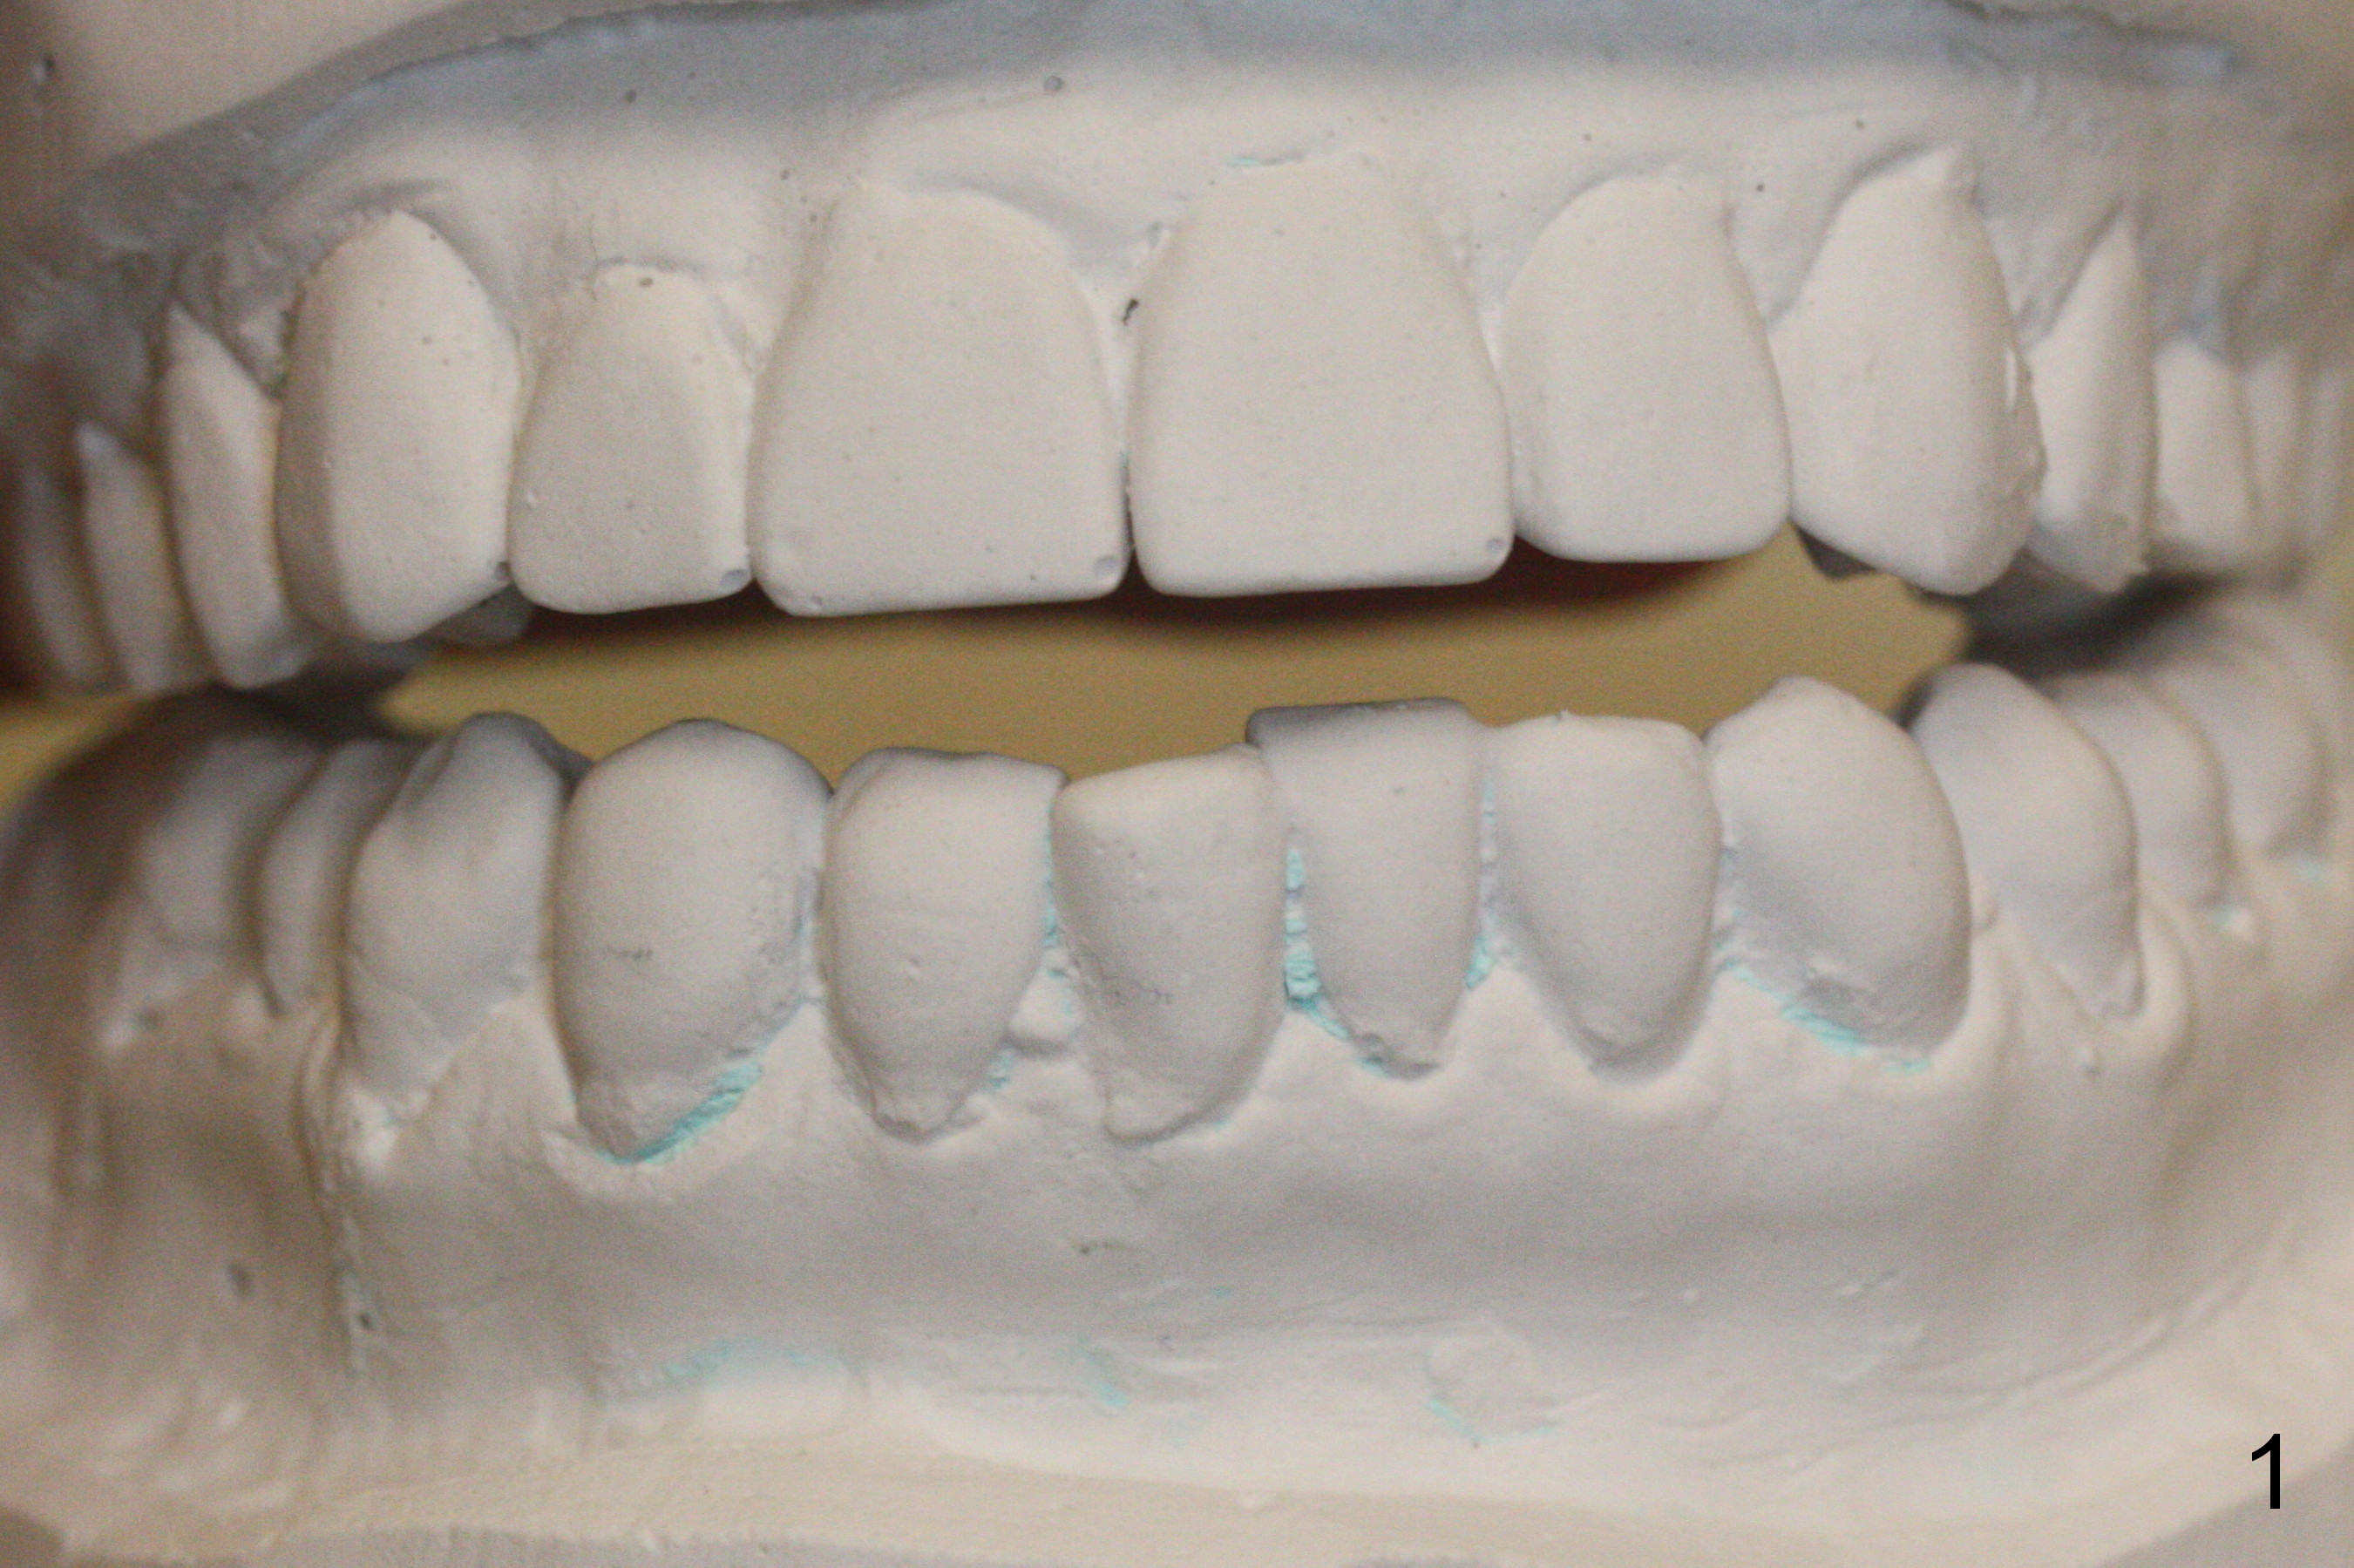

Wax Up for Lower Anterior Veneers

A 46-year-old woman has Tetracycline teeth. She is pleased with upper veneers and wants to do the same for the lower anterior teeth, which are crowding (Fig.1,2). Wax up (Fig.3,4) lays foundation for fabrication of reduction and provisional stents.